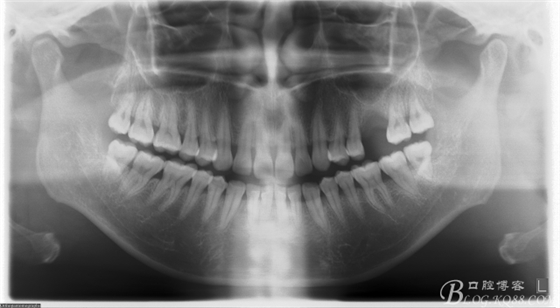

患者唐某某,男,50歲,要求種植修復(fù)左上缺失大牙。

術(shù)前X片。